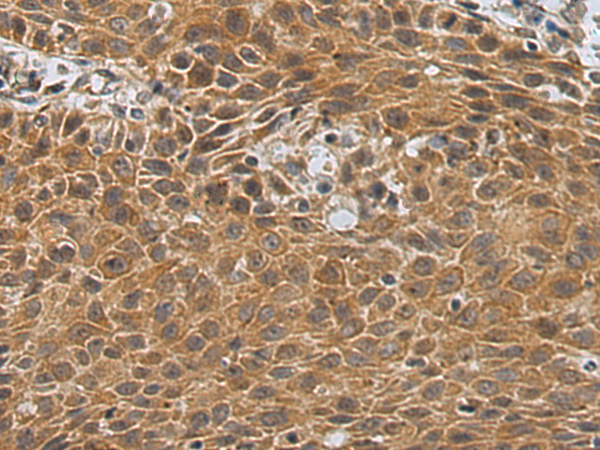

IHC positive control: |

Human esophagus cancer |

IHC Recommend dilution: |

150-300 |